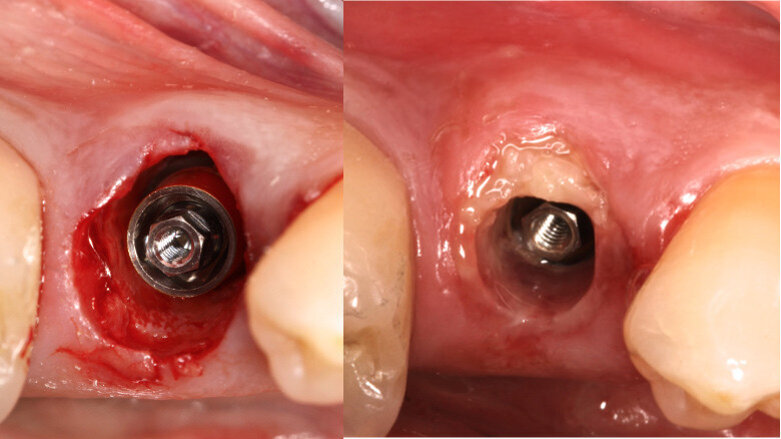

A 5 x 15 mm BTI interna plus implant (internal connection) was placed lingually to the SS, taking as reference for 3D positioning the adjacent tooth and implant crowns. The platform of the implant was placed 1 mm below the level of the buccal bone crest and the SS (Fig. 3). A BTI UNIT Transepithelial abutment was used to extend the implant’s platform 0.5 mm subgingivally (Fig. 4).

The gap distance inside the socket between the implant and the SS was filled solely with plasma rich in growth factor (Endoret, BTI Biotechnology Institute; Fig. 5). A final zirconia crown was fabricated and placed 24 hours after surgery. It was entirely designed and fabricated using the Zirkonzahn CAD/CAM system (Figs. 6–8).

Fig. 3: Implant without intermediate abutment.

Fig. 4: Implant with intermediate abutment.

Fig. 5: The gap distance between the implant and the SS was filled solely with Endoret.